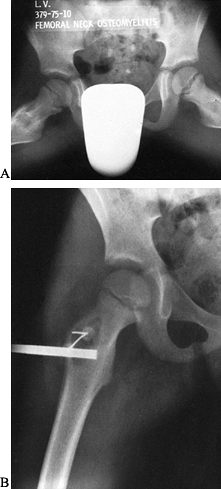

generally in the metaphyseal region. It is also important to evaluate

the adjoining joint for evidence of septic arthritis, which can occur

as an extension of the adjoining osteomyelitis. Osteomyelitis involving

the neck of the femur, talus, and humeral head often leads to sepsis of

the joint because these foci are located within the joint capsule.